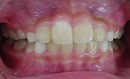

さて、この様な歯並びの方はかなり見受けられると思われます。

→

当矯正歯科医院では、咬合バランスを改善する為には、

顎骨の拡大だけでは不十分と考えています。

その為、かみ合わせの高さなどを立体的に改善していく事を心がけて日々治療しています。

今回も治療には、独自の方法とビムラー装置・t4k等を利用して改善しました。